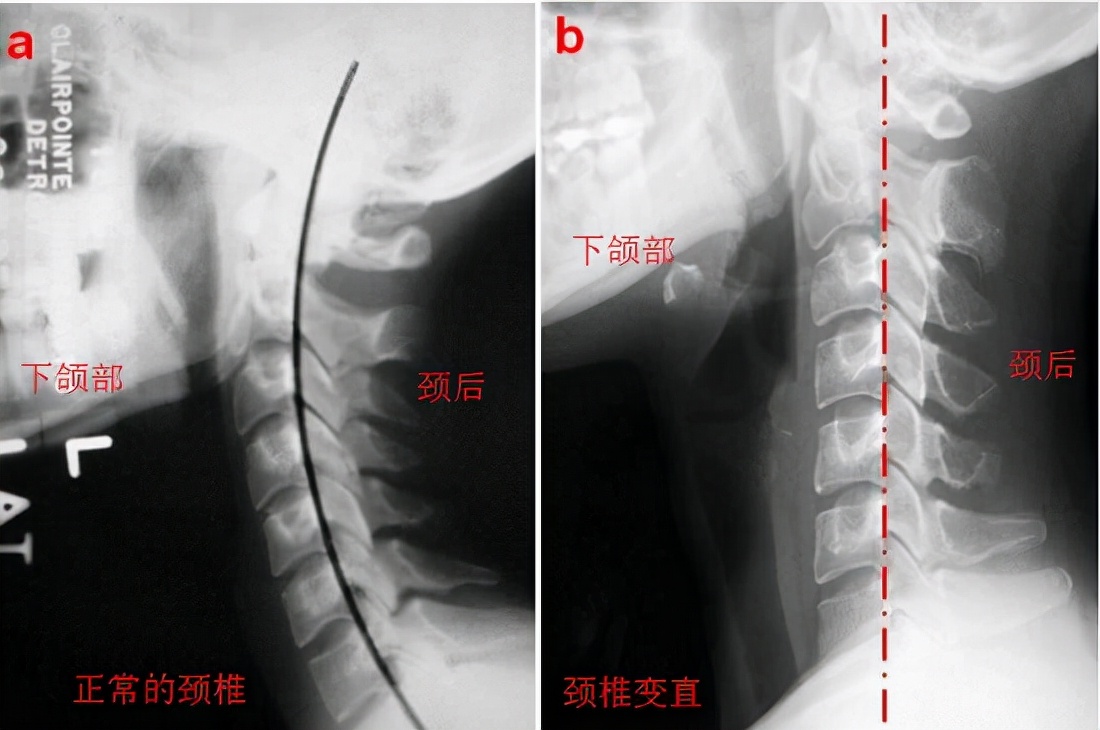

还有个动作叫“蝴蝶式”:站姿、坐姿均可,上身直立,将双手抱于枕后,使上臂形成“蝴蝶”的样子;然后在呼气的同时,尽力低头、弓背、双臂向内收(在疼痛范围内,循序渐进);吸气时,抬头、直立上身,双臂向外展使其回到初始动作。该动作每组做10-20个,每天2-3组,可使颈部、前胸以及后背的肌肉得到锻炼,缓解颈部疼痛。长时间伏案工作或者低头看手机也会造成颈部疼痛,这种疼痛与颈部后面的肌肉长时间牵拉、颈部前方的肌肉长时间收缩有关,同样可通过康复锻炼加以缓解。“低头族”可以用收颌(也就是收下巴)的动作锻炼:站姿、坐姿均可,上身直立,下颌在不疼痛的范围内尽量往回收(疼痛说明可能有肌纤维缩短的情况),坚持20秒。该动作可使颈椎深层稳定肌得到锻炼,也能使椎间孔拉开,使椎间孔狭窄导致的症状得到缓解。